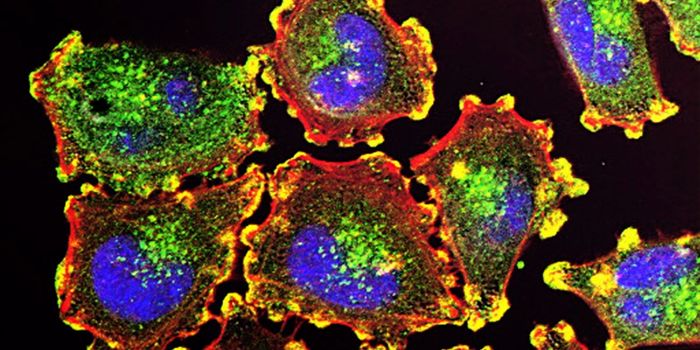

MAR 27, 2023CancerThe tumor microenvironment (TME) consists of the cells, healthy and malignant, molecules, and blood vessels, surrounding ...